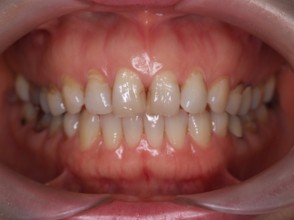

| 主訴 | 過去作成した右下の被せ物がずれて入っており、たまに腫れる。歯並びも気になる。 |

| 治療内容 | 矯正治療を行いました。 |

| 治療費 | 800,000円(税込み) |

| 治療期間 | 2年半(矯正治療期間 2年) |

| 治療回数 | 30回 |

| 想定されたリスク | 術前に基礎資料を整え分析し、セットアップモデル等でシミュレーションをしておかないと、予定通りの治療が行えないリスクがあった。 |